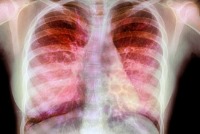

شفیعیان ادامه داد: با این تست میتوان برخی بیماریها و پاسخ آنها به درمان را پیگیری کرد و در بررسی بیماران مبتلا به سرفه مزمن، تنگی نفس یا رادیوگرافی غیرطبیعی از قفسهسینه کاربرد دارد.

این محقق با اشاره به دیگر کاربردهای تست اسپیرومتری، اظهار کرد: همچنین در ارزیابی کلی شدت بیماریهای انسدادی و تحدیدی ریه، بررسی پاسخ بیمار به داروهای گشادکننده برونش، پیشبینی ریسک اعمال جراحی این تست کاربرد دارد.

وی با بیان اینکه اسپیرومتری برای تعیین ناتوانی تنفسی در بیماریهای شغلی بهکار میرود، افزود: اهداف اسپیرومتری ارزیابی فعالیت پایه ریهها و تست غربالگری و تشخیص زودرس برخی بیماریهای ریه بوده که فاقد علائم بارز هستند. این آزمایش ناتوانی تنفسی در بیماریهای شغلی را تعیین میکند.